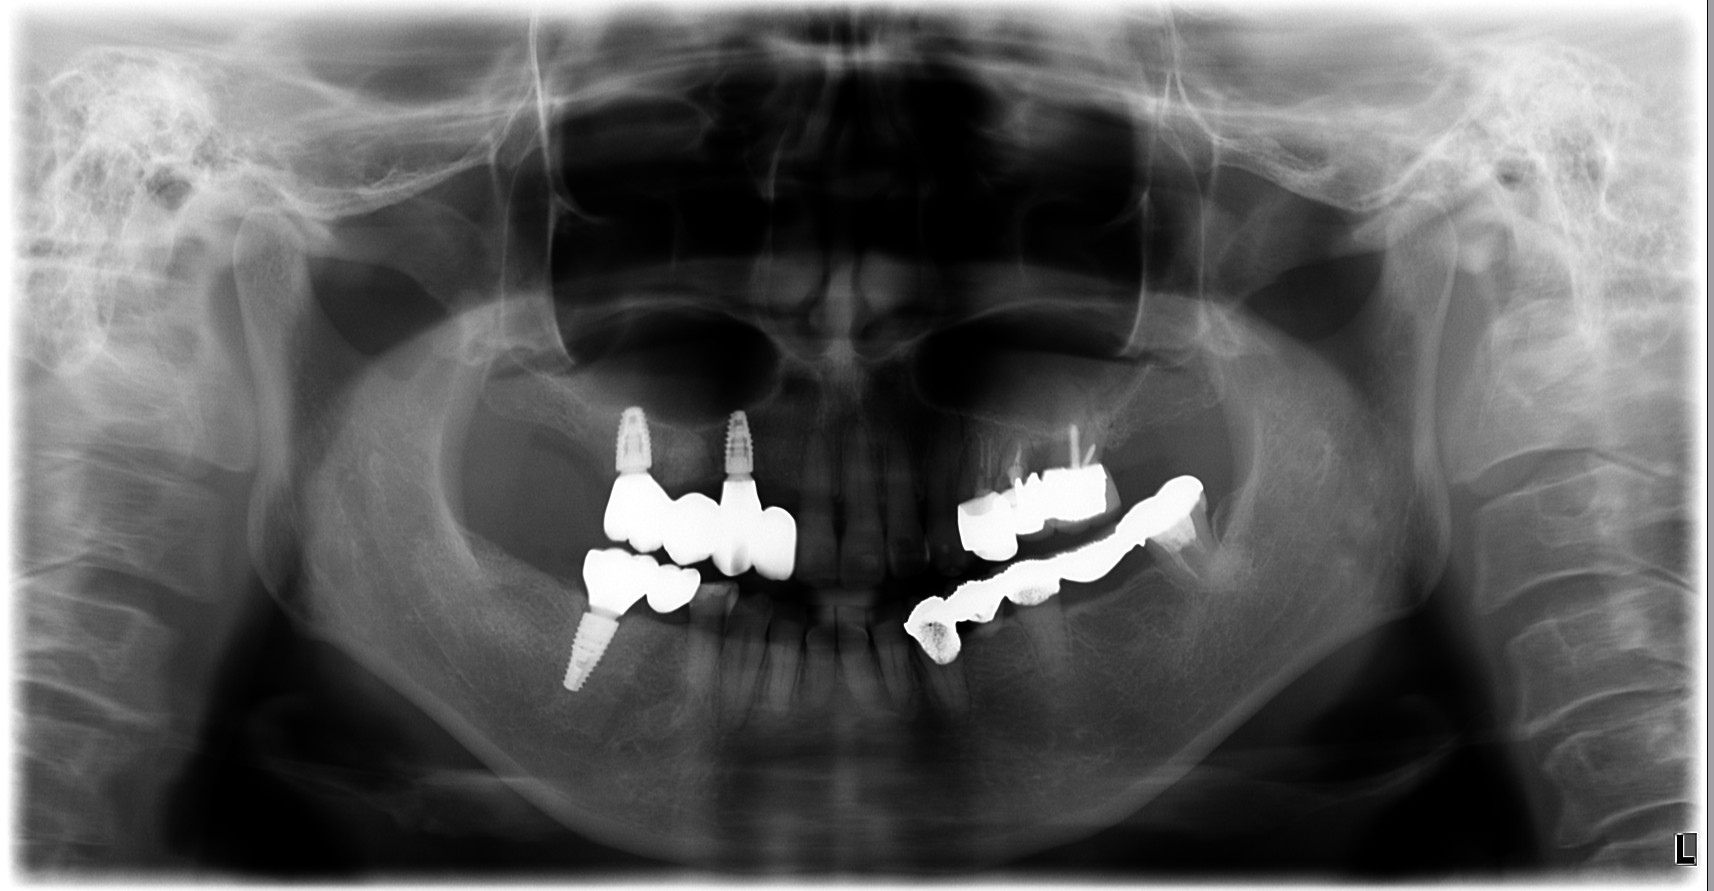

治療後

| 治療内容 | 初診時の考え方:原因は「歯」だけではなく“設計”のことがある 腫れや動揺があると、「歯周病だから」「根が悪いから」と言われがちですが、再治療で大切なのは なぜその状態まで進んだのかを整理することです。 補綴(被せ物・ブリッジ等)の設計や噛み合わせに無理があると、特定部位に力が集中して • 炎症(腫れ・排膿) • 動揺(グラつき) • 噛めない という状態に進行することがあります。 このケースも、力のかかり方を見直し、噛み合わせと補綴設計を再構成することが治療の軸になりました。 ⸻ 奥歯が噛めない → 前歯が働きすぎて切端咬合になっていた 患者様は「奥歯で噛めない」状態を補うように、前方で噛む癖がつき、 切端咬合(前歯同士がぶつかる噛み方)になっていました。 切端咬合は、 • 前歯が欠けやすい/すり減りやすい • 補綴が壊れやすい • 力の逃げ場がなくなる など、治療後の安定を難しくする要因になります。 そのため今回は、インプラント治療だけで完結させるのではなく、前歯の噛み合わせも作り直す必要がありました。 ⸻ 治療方針:本数を増やすのではなく“成立させる条件”を整える 患者様の条件(費用・怖さ・体の負担)を踏まえ、当院では • インプラントは3本に絞る • 上下ともにインプラントブリッジで噛める機能を回復 • 部分矯正で切端咬合を改善し、少ない本数でも成立する咬合へ • 可能な範囲で抜歯即時を選択し、外科を1回にまとめる という方針を採用しました。 ⸻ 治療のポイント①:部分矯正は“見た目”ではなく、設計を成立させるために使う 本数を絞った設計を成立させるには、力のかけ方(咬合設計)を整えることが重要です。 そこで、部分矯正で • 前歯の被蓋(かみ合わせ)を再構築 • 前歯に負担が集中しない状態へ • ブリッジに無理が出ない噛み合わせへ と調整し、少ない本数でも長期安定を狙える条件に近づけました。 ⸻ 治療のポイント②:上下インプラントブリッジ+材料選択(高強度ジルコニア) 上下ともにブリッジ設計の場合、材料と厚みの設計が安定性に直結します。 今回は、審美性や立体感はやや制限される可能性がある一方で、 強度を優先できる高強度ジルコニアを選択し、必要な厚みを確保しました。 「見た目の理想」よりも、まずは 噛めること/壊れにくいこと/長く使えること を優先した設計です。 ⸻ 治療のポイント③:抜歯即時で外科は1回にまとめる 患者様の「手術が怖い」「回数を減らしたい」という希望に対して、 感染や骨の条件を見極めたうえで、可能な範囲で抜歯と同日にインプラント埋入(抜歯即時)を行い、外科介入を1回にまとめました。 ※抜歯即時は、すべてのケースに適応できる方法ではありません。 ⸻ 治療後の経過(結果) • 噛めない状態が改善し、食事の不安が軽減 • 切端咬合を改善し、前歯の負担を減らす方向へ • 少ない本数でも成立するよう、噛み合わせと設計を最優先で再構成 ⸻ 担当医コメント 「理想形」だけを追うと、治療は大きくなりがちです。 今回のように、患者様の希望(負担・回数・費用)を尊重しながら、噛み合わせと設計を整えることで“成立させる治療”を選ぶことも大切だと考えています。 |